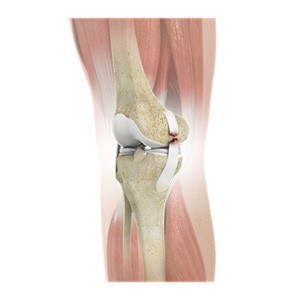

Picture of Knee Arthritis

Knee Arthritis

The joint surface is covered by a smooth articular surface that allows pain-free movement in the joint. Arthritis is a general term covering numerous conditions where the joint surface or cartilage wears out. This surface can wear out for several reasons; often the definite cause is not known. Arthritis often affects the knee joint. When the articular cartilage wears out, the bone ends rub on one another and cause pain. The most common type of arthritis is osteoarthritis. It occurs with ageing and use.